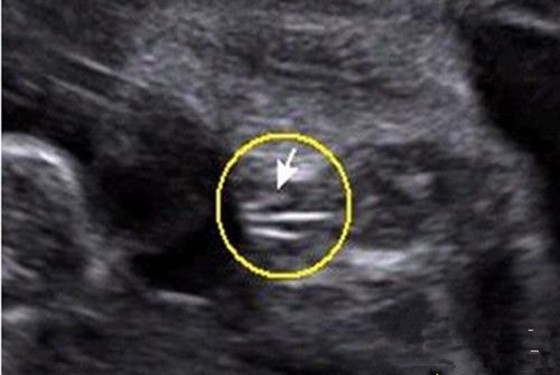

2、女宝宝的b超图:三条白线是明显的女宝特征,如果没有看到明显的三条白线,就看两腿之间有没有突出的东东,且中间有小凹槽的,就是女宝宝。